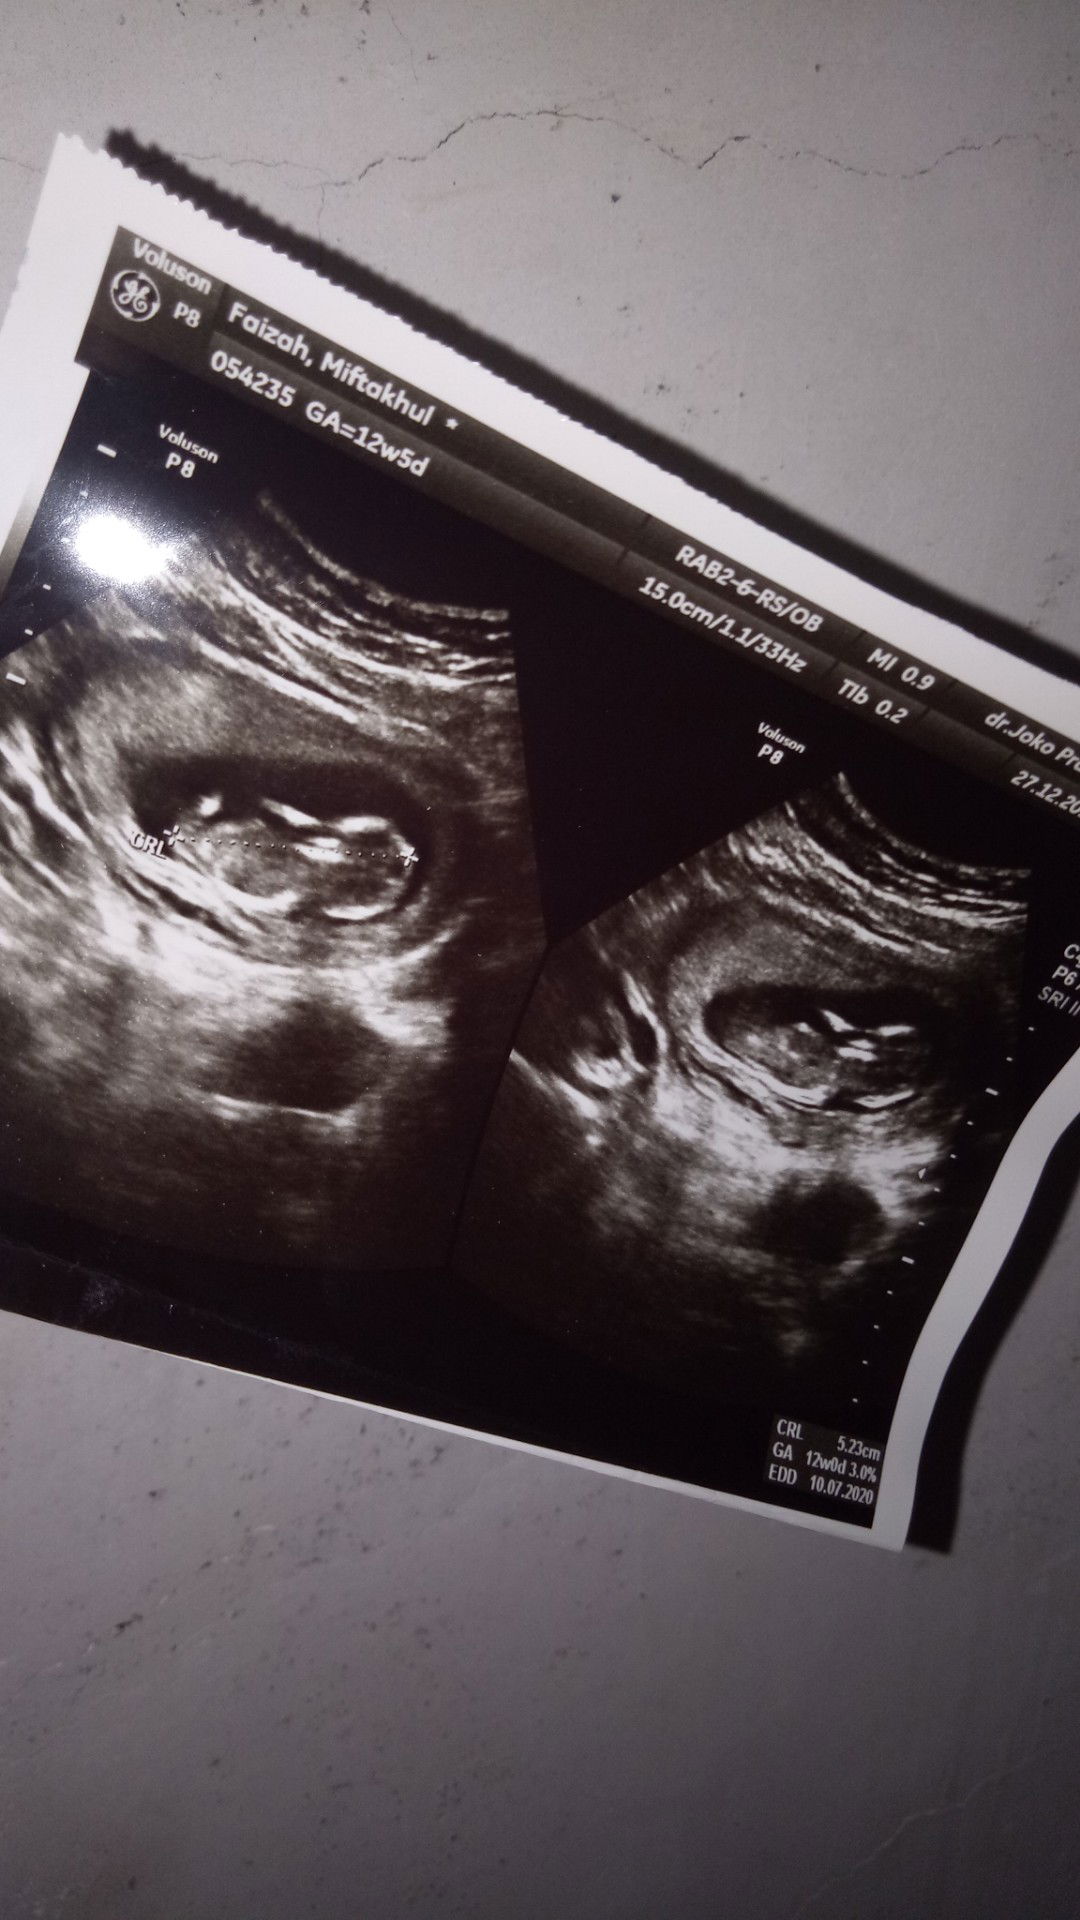

usg 3 bln

Bun. Mau tanya donk. Usg ku 3 bulan penampakannya gini. Hhe.. Ada yg comment klo itu kembar. Mnurut bunda gmn? Kali aja prnh hamil kembar atau saudaranya

Waktu usg dokternya bilang gimana bu? Bilang kembar ga? Biasanya untuk kehamilan kembar dokternya lebih ngasih perhatian khusus dan pasti dikasih tau dokternya. Tapi sepertinya itu kehamilan tunggal kok.